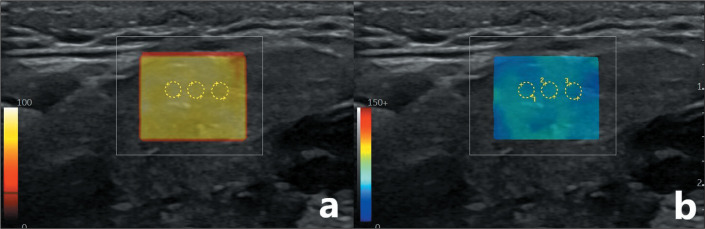

Materials and methods: This was a prospective controlled study of patients diagnosed with AS and exhibiting sicca symptoms (study group) and of healthy volunteers (control group). The levels of antinuclear, anti-Ro, and anti-La antibodies were determined in blood samples. In both groups, parotid and submandibular glands were evaluated by ultrasound and tissue stiffness was determined by SWE. Intraclass correlation coefficients were used in order to assess reliability. The differences between the two groups were assessed by statistical methods, and a ROC curve analysis was performed to determine the predictive values.

Results: A total of 66 patients with AS and 71 healthy volunteers were included in the study. There were no significant differences between the groups in terms of age or sex (p > 0.05). The intraand inter-rater reliability of SWE were good for the parotid gland (0.81-0.85 and 0.80, respectively) and for the submandibular gland (0.85-0.88 and 0.80, respectively). Statistically significant differences were found. Tissue stiffness in the parotid and submandibular glands, as determined by SWE, was significantly greater in the study group than in the control group (p < 0.05).